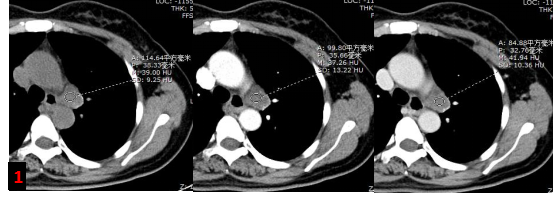

胸部強化CT?

主動脈弓左旁不規則混雜密度腫塊影,增強未見明顯強化,考慮腫大淋巴結,轉移灶?(圖1)